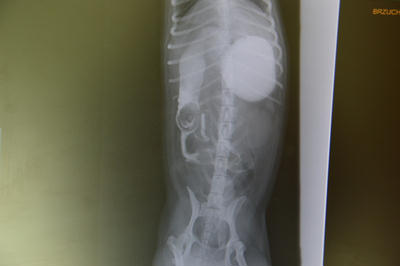

Ciało obce w dwunastnicy uwidocznione dzięki podaniu kontrastu.